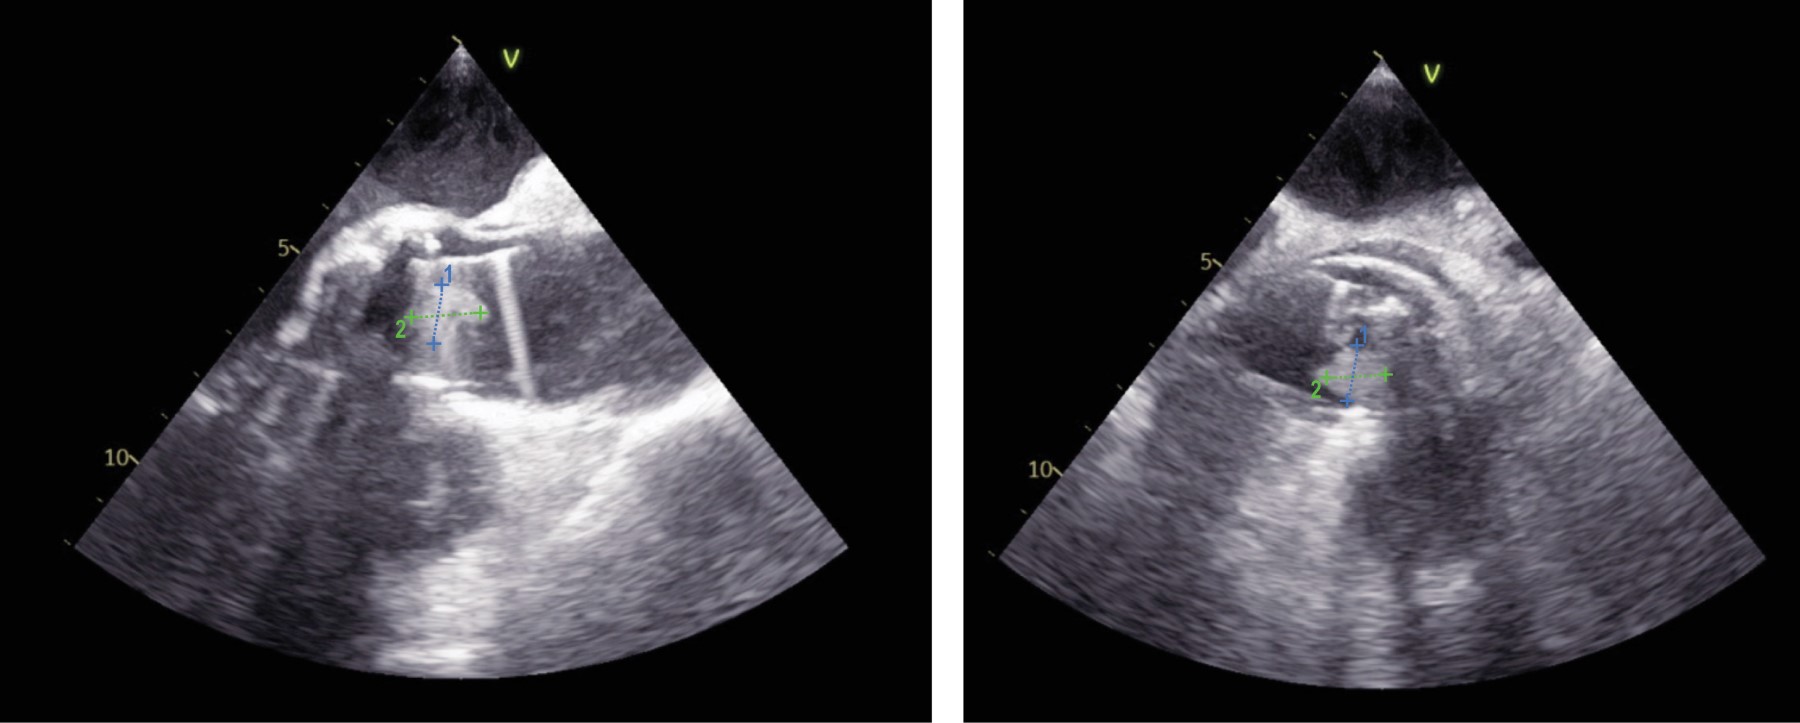

Figura 1

Figura 2

Figura 3

Figura 4

Figura 5